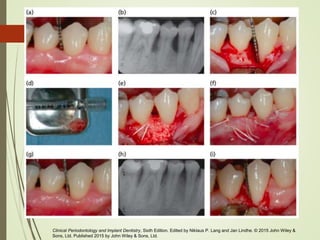

Examen radiografico

Las imágenes en radiografías y tomografías

proporcionan información más precisa

Facilitan el diagnostico y guían el

tratamiento a elegir

Diagnosis and Treatment of Furcation-Involved Teeth, First Edition. Edited by Luigi Nibali. © 2018 John Wiley & Sons Ltd. Published

2018 by John Wiley & Sons Ltd.

Clinical Periodontology and Implant Dentistry, Sixth Edition. Edited by Niklaus P. Lang and Jan Lindhe. © 2015 John Wiley & Sons,

Ltd. Published 2015 by John Wiley & Sons, Ltd.

La detección del defecto, su ubicación

y extensión, junto con sus principales

características morfológicas solo se

pueden confirmar con la elevación del

colgajo